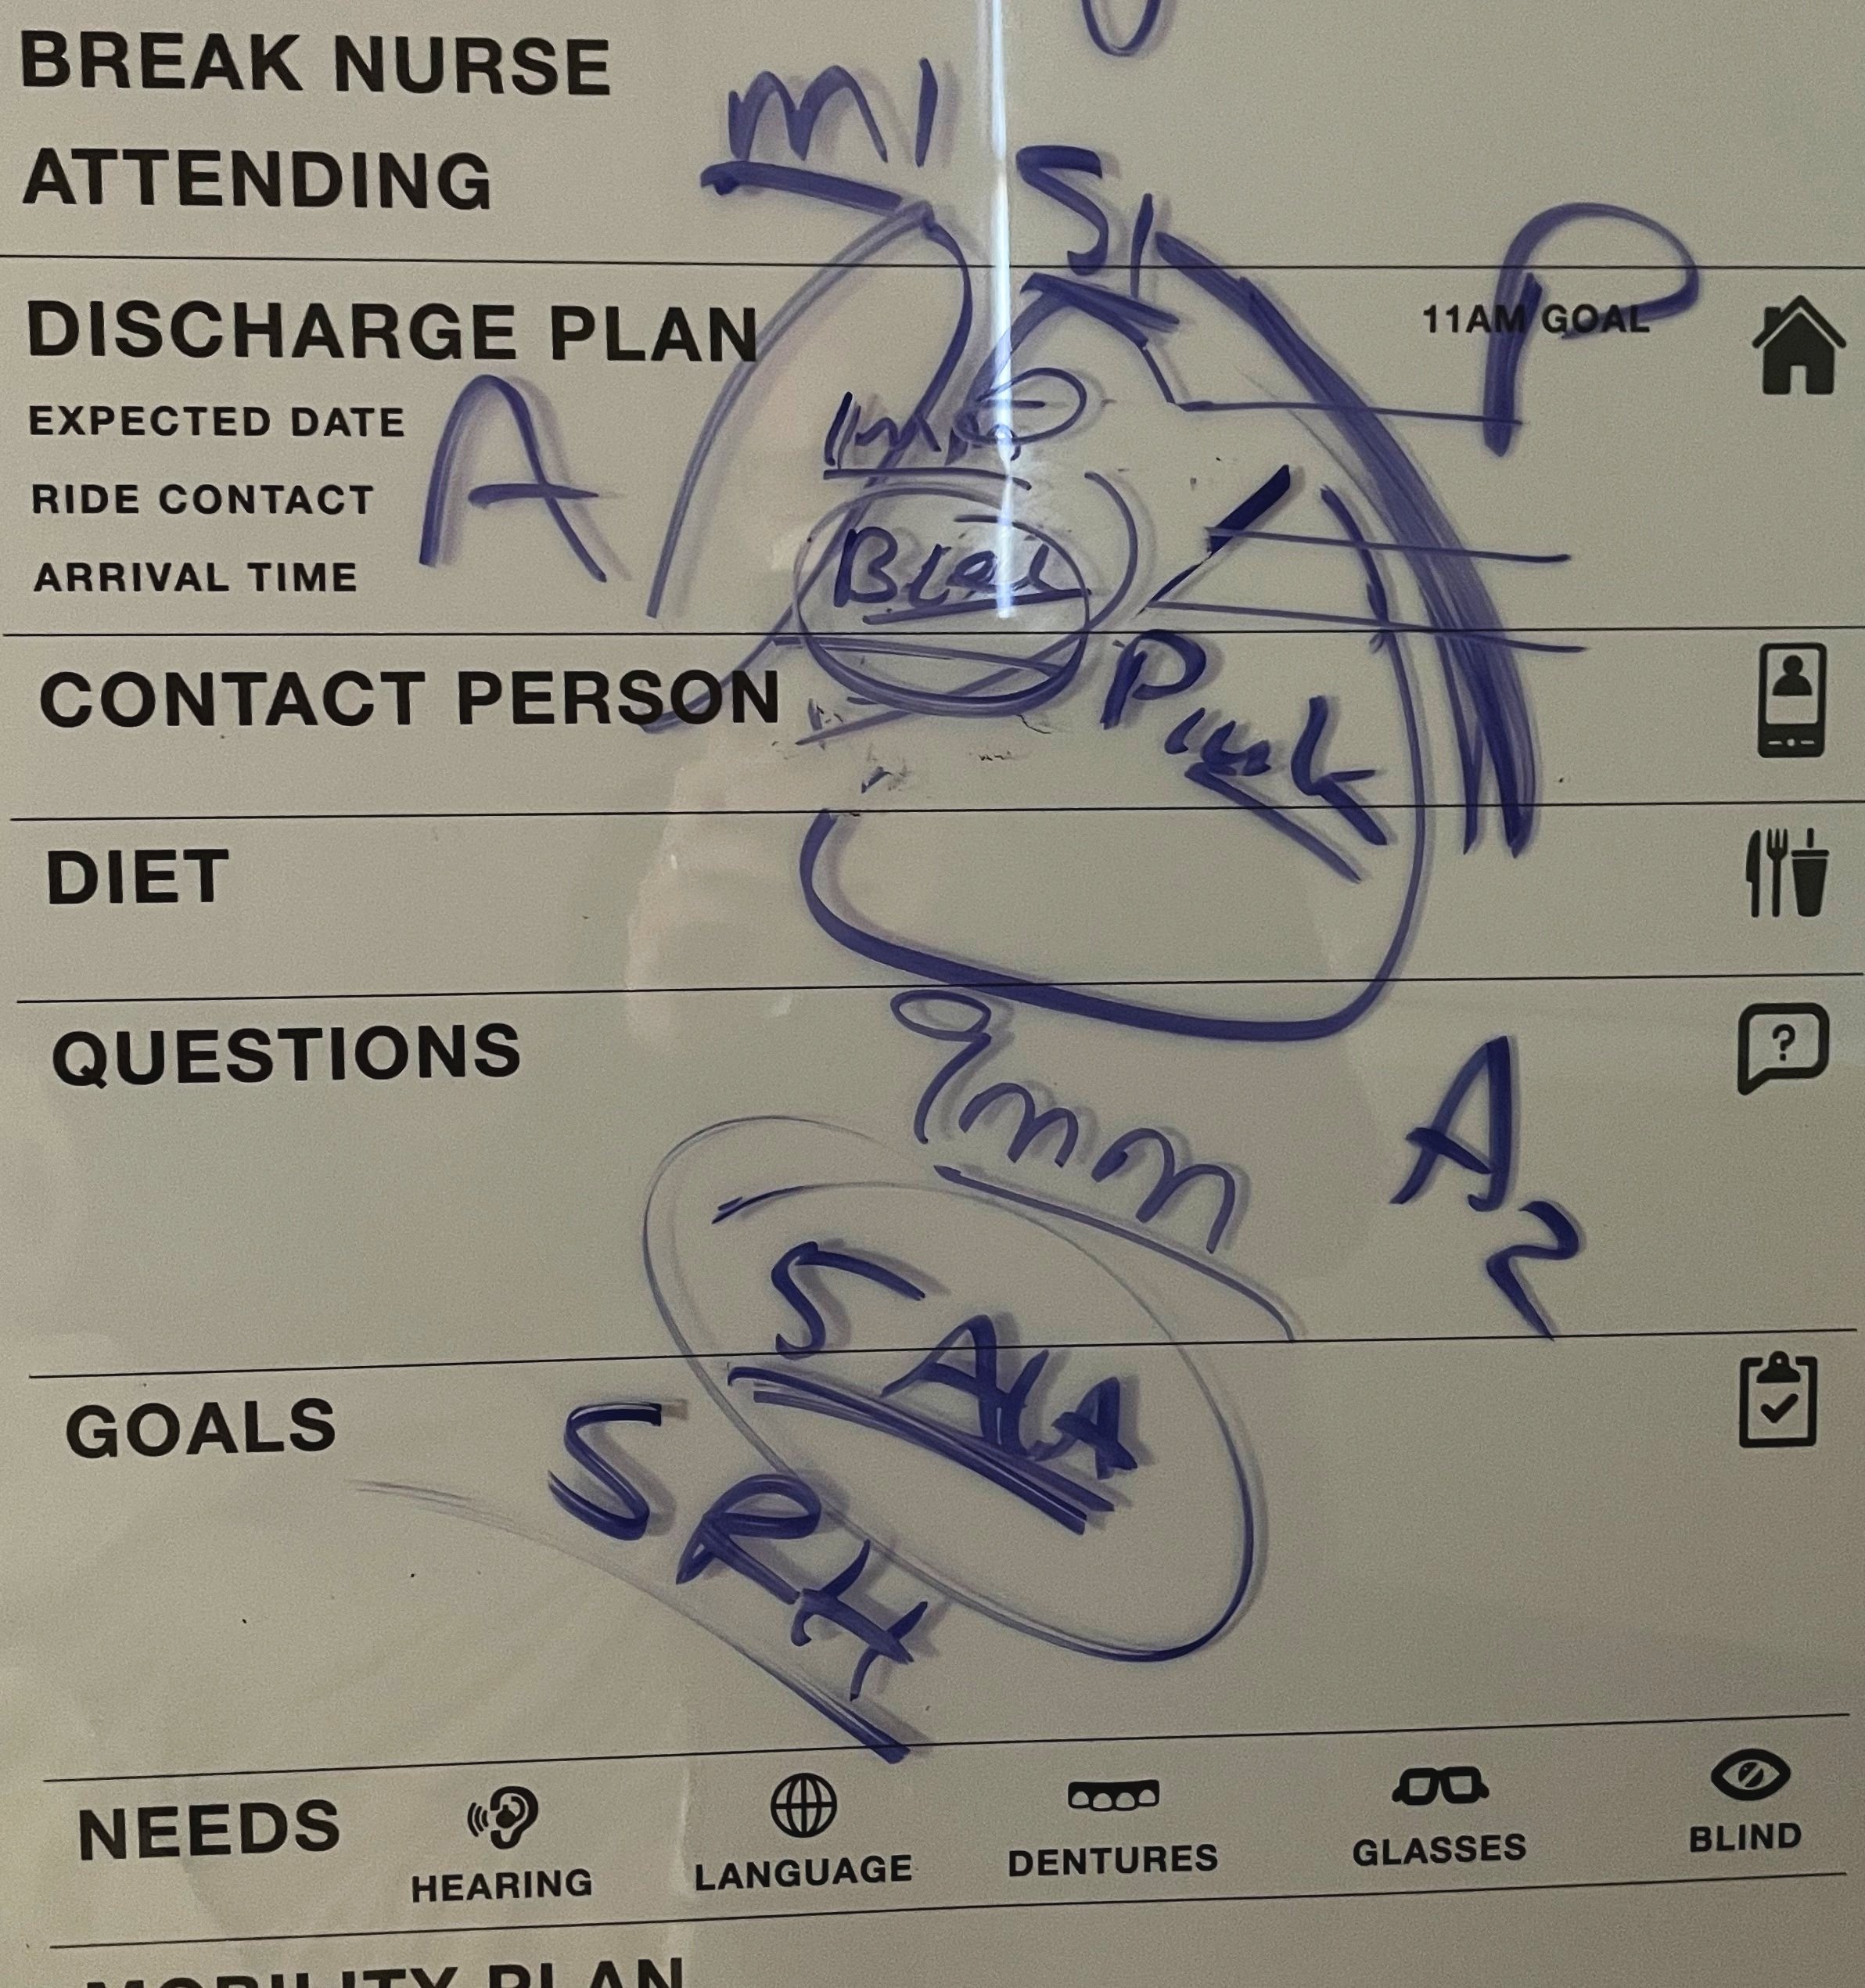

Living with a slow growing brain cancer

My favorite part about research is learning new things in real time. Here I share my observations as a learner and my n of 1 (personal) findings as a patient.